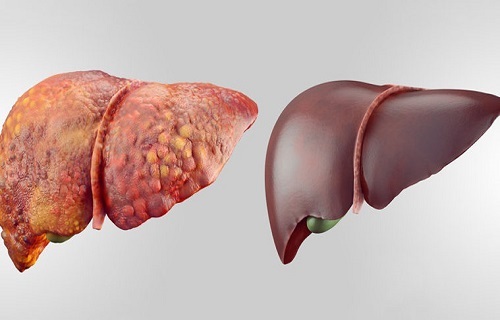

از دشمنان کبد خود غافل نشوید

آفتابنیوز : شهرام آگاه متخصص گوارش و کبد درباره مواد آسیب رسان به کبد و راههای مراقبت از آن اظهار…